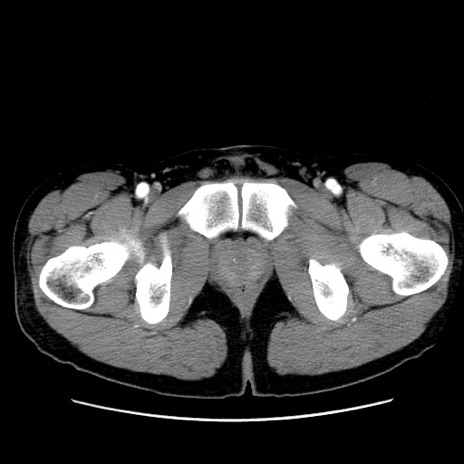

症例36(横断像)

【症例】20歳代 男性

【主訴】心窩部痛

【現病歴】今朝より上腹部痛あり。一旦軽快していたが再度出現したため救急要請。昨日夕に白身の魚を含む刺身を食べた。

【身体所見】BP 136/89mmHg、HR 74/min、BT 37.0℃、腹部:膨満、軟、心窩部に圧痛あり。反跳痛なし、筋性防御なし、腸雑音やや亢進あり。

【データ】WBC 17700、CRP 0.48